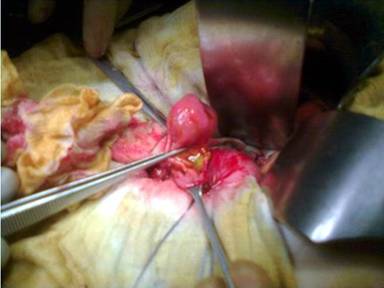

Computed tomography recognized a mass of the duodenum (Figure 1). However, magnetic resonance imaging did not reveal any lesion. Radiological differential diagnosis included gastrointestinal stromal tumor or adenoma. A magnetic resonance cholangiopancreatography was performed showing dilatation of the common bile duct (diameter equal to 9 mm) and gradually narrowing of its diameter downwards. Endoscopic retrograde cholangiopancreatography (ERCP) revealed a submucosal tumor located in the second portion of the duodenum. The lesion was seen as a large pedunculated polypoid mass originating from the second part of the duodenum in close proximity with the ampulla of Vater (Figures 2 and 3). No cholangiography was performed due to failure of cannulation of the bile duct. The pancreatic duct was normal without dilatation in its body or narrowing of its size. A sphincterotomy was performed 6 mm along the pancreatic sphincter, as it is considered an endoscopic therapy for chronic pancreatitis with papillary stenosis [8]. Two months after the procedure of sphincterotomy, the patient had another episode of acute pancreatitis without jaundice. Hence, the obstruction of the pancreatic duct due to the intermittent movements of the mass was considered as the cause of the episodes of acute pancreatitis. The patient was referred for surgical consultation and regional resection was decided. The operation was performed one month after the last episode of acute pancreatitis. Intraoperatively (Figure 4), there was no sign of lymph node metastases or local extension of the tumor.

Figure 4. Α polypoid mass in the second portion (periampullary) of the duodenum: intraoperative aspect. |